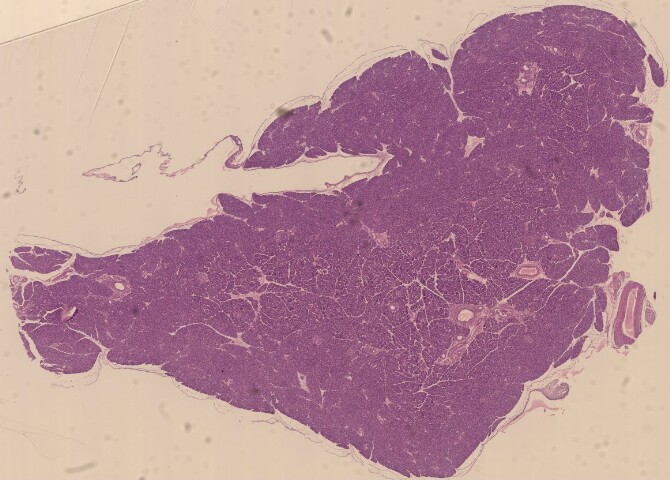

Pancreas. Colorazione: ematossilina ed eosina

Sezione del parenchima pancreatico.

Vetrino istologico - insegnamento Istologia ed Embriologia.